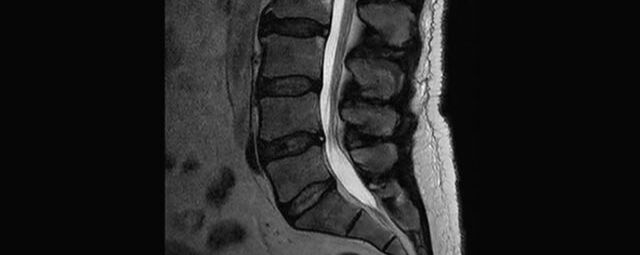

- Abklärung Bandscheibenvorfall

- Beurteilung Einengung des Rückenmarkkanals oder der Neuroforamina im Rahmen der degenerativen Wirbelsäulenerkrankung

- Tumor-/Entzündungsdiagnostik

- Multiple Sklerose

- Abklärung Spondylolisthesis

- Frakturdiagnostik (Alter und Ausdehnung der Fraktur) z.B. im Rahmen der Osteoporose